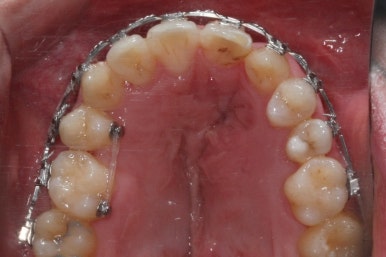

부산구순구개열 키다리아저씨치과에 처음 오셨을 때의 입 안의 모습입니다.

입천장이 갈라져서 어릴 때 봉합 수술을 했기 때문에 그 상처가 굵게 남아있는 것을 볼 수 있습니다. 일반적으로 피부상처도 다른 부위보다 단단하듯이 입천장의 봉합 상처도 매우 단단하게 아물기 때문에 성장에 방해를 주게 됩니다.

가로폭이 매우 좁고 찌그러져 있습니다.

또한 위턱이 앞으로 자라나는 것도 방해해 대부분 앞니가 거꾸로 물리게 됩니다.

또한 가랄져 있던 선에 걸쳐 있는 영구치 일부는 선천결손이 되는 경우가 많습니다.

이번 환자분도 이런 특징을 모두 갖고 계셨습니다.

악궁확장이 시작될 시점과 악궁확장을 다 진행했을 시점의 비교입니다.

확실히 좁아져 있던 가로 넓이가 넓어진 것을 볼 수 있습니다.

좁아져 있고 찌그러진 위턱뼈의 형태가 개선되었습니다.